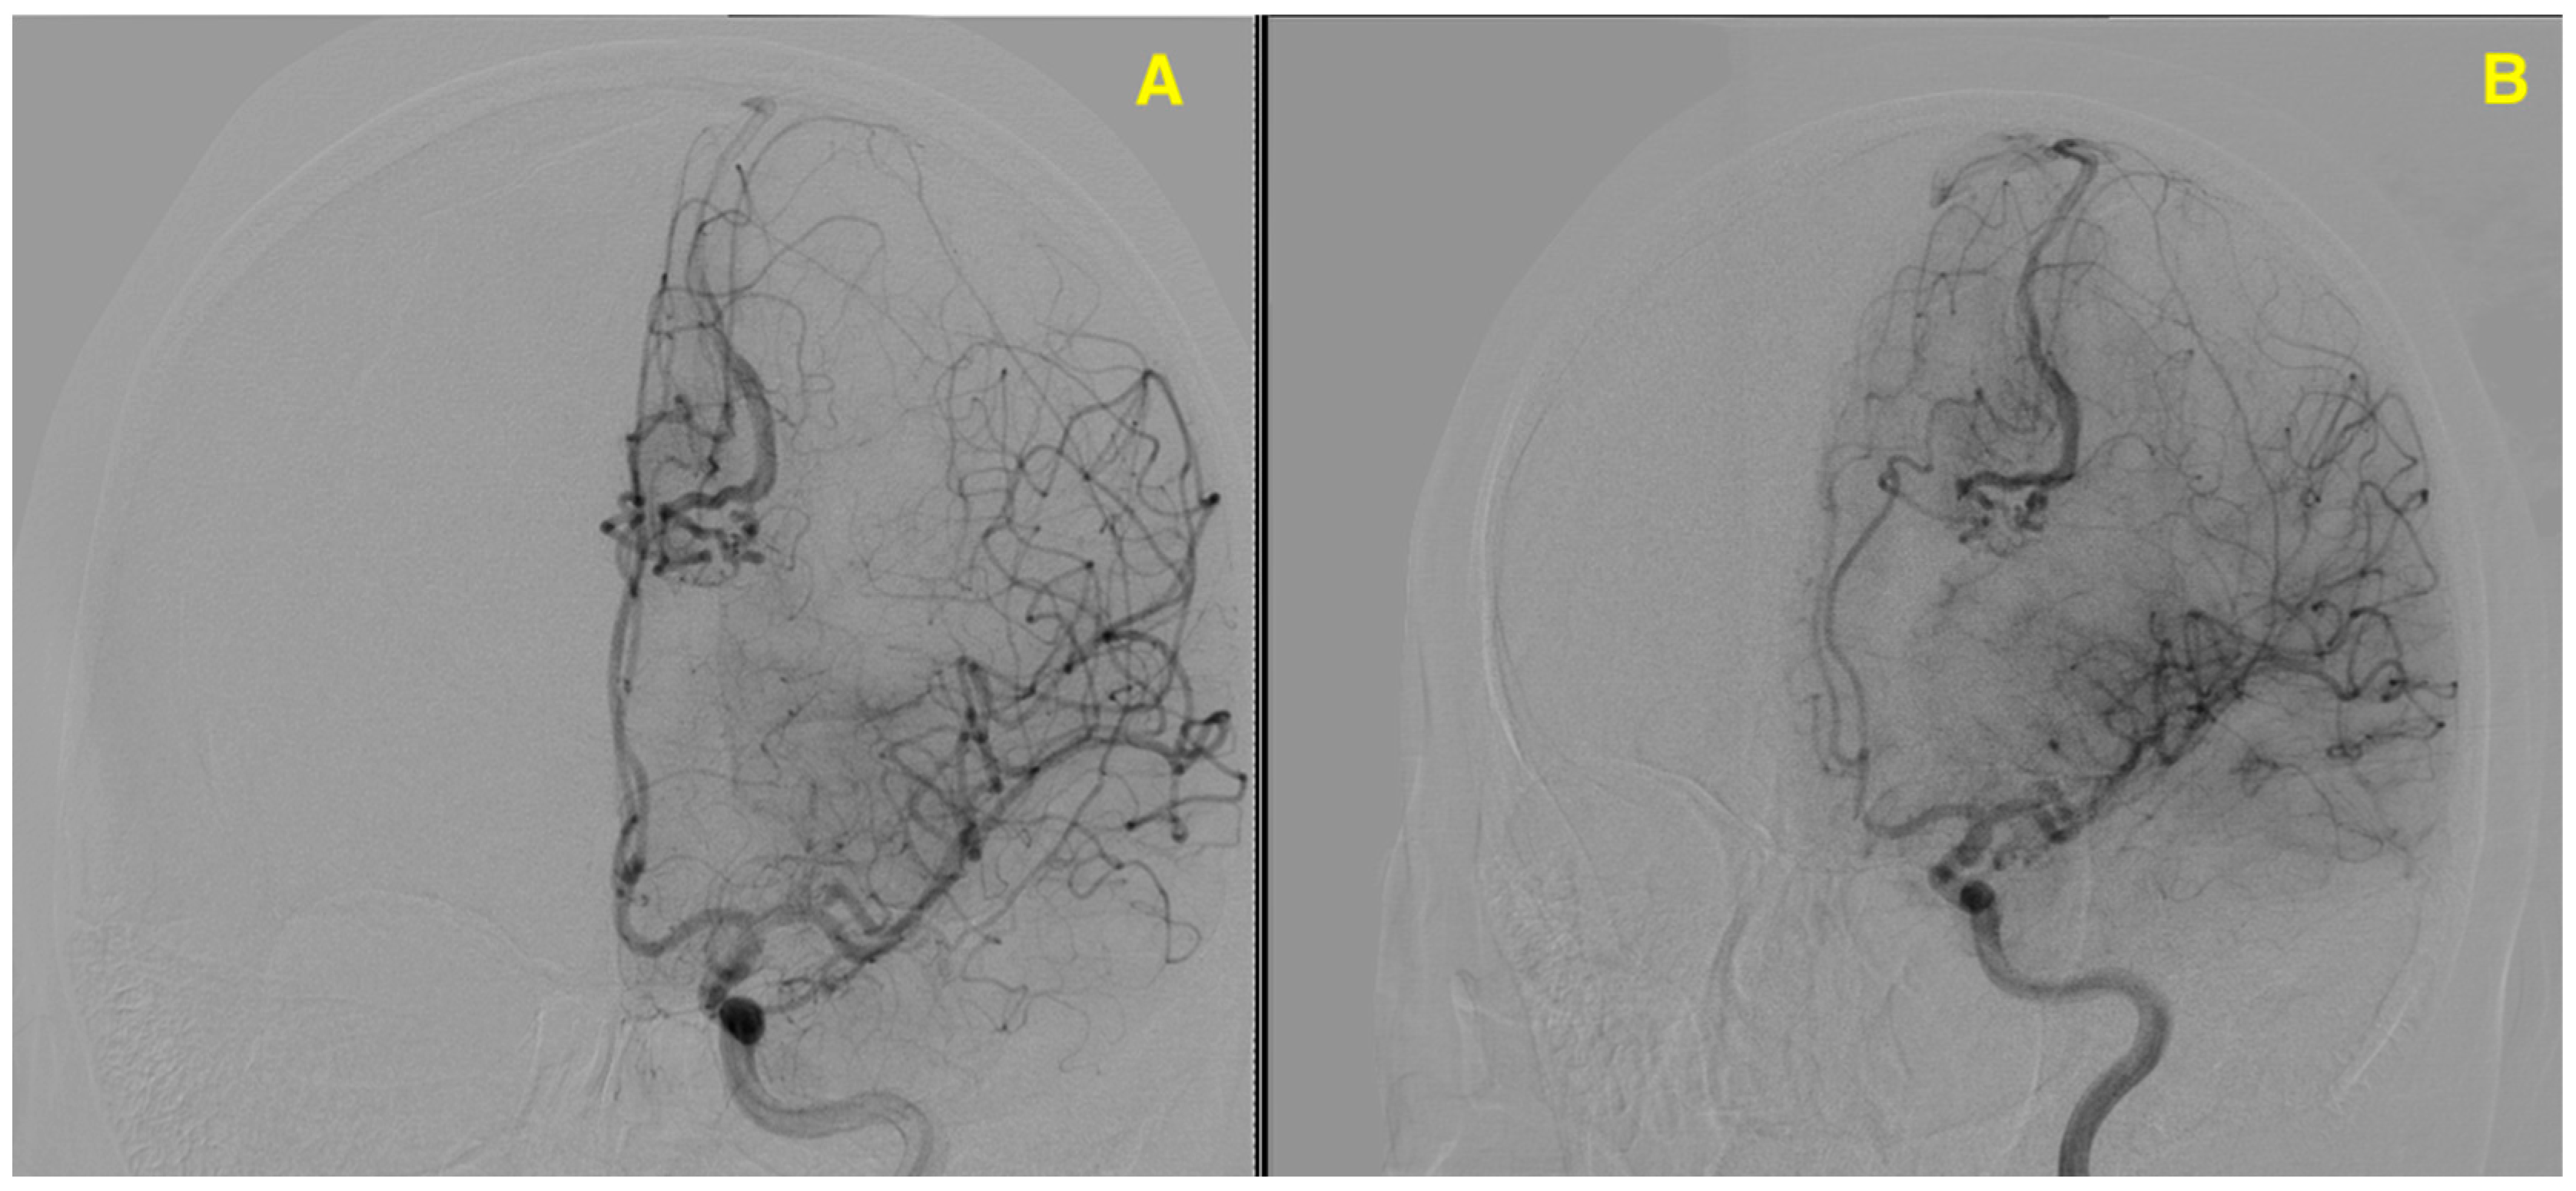

Challenging Management of a Rare Complex Cerebral Arteriovenous Malformation in the Corpus Callosum and Post-Central Gyrus: A Case Study of a 41-Year-Old Female

2. Case Presentation